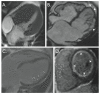

Cardiovascular magnetic resonance (CMR) has expanded its role in the diagnosis and management of congenital heart disease (CHD) and acquired heart disease in pediatric patients. Ongoing technological advancements in both data acquisition and data presentation have enabled CMR to be integrated into clinical practice with increasing understanding of the advantages and limitations of the technique by pediatric cardiologists and congenital heart surgeons. Importantly, the combination of exquisite 3D anatomy with physiological data enables CMR to provide a unique perspective for the management of many patients with CHD. Imaging small children with CHD is challenging, and in this article we will review the technical adjustments, imaging protocols and application of CMR in the pediatric population.